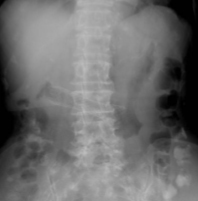

腹部レントゲン検査および腹部CT検査によって閉塞部位を同定します。また同時に、消化管閉塞の部位が複数ないことを確認します。その後、消化管造影検査や内視鏡検査によって実際の消化管閉塞の詳細を評価します。